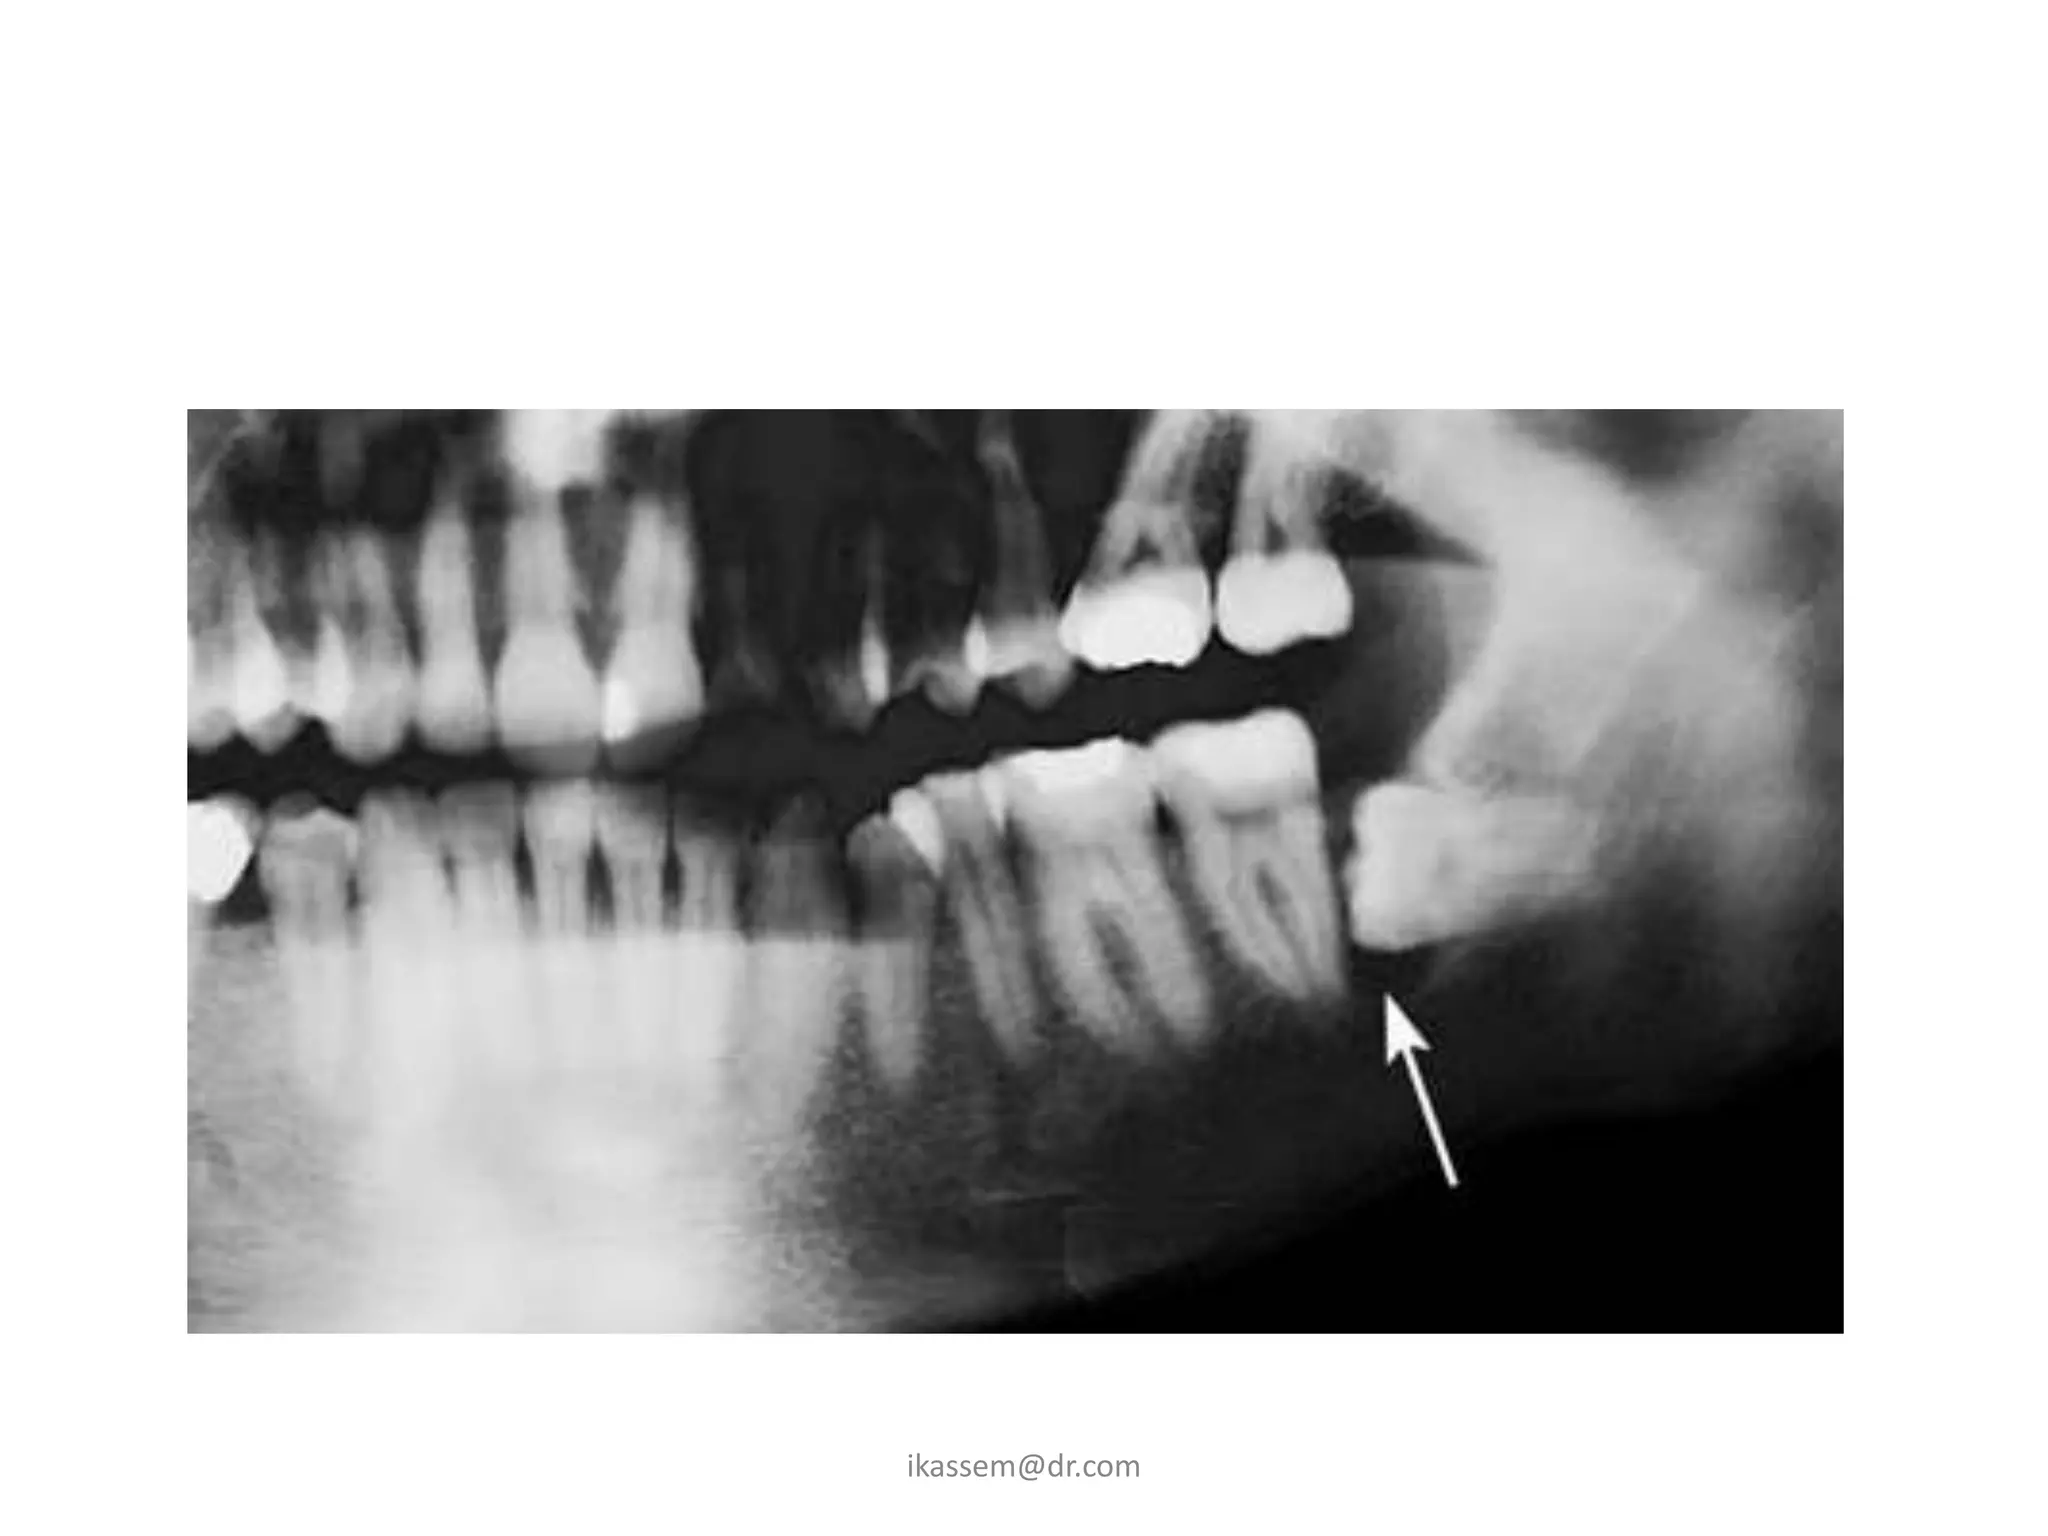

B. Dental Caries

• When third molar is

impacted or partially

impacted ,the bacteria

that cause dental caries

can be exposed to the

distal aspect of the 2nd

molar, as well as to

third molar

C. Periodontal Disease

• Erupted teeth adjacent to

impacted teeth are

predisposed to periodontal

disease.

• As it decrease amount of bone

on the distal aspect of adjacent

2nd molar, with deep

periodontal pocket on the

distal aspect of the 2nd molar.

D. Root Resorption

• Impacted teeth cause

sufficient pressure on

the root of an adjacent

tooth to cause root

resorption.